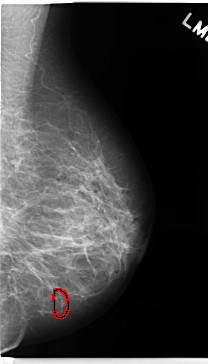

C_0239_1.RIGHT_MLO

LEFT_MLO LINES 4728 PIXELS_PER_LINE 2696 BITS_PER_PIXEL 12 RESOLUTION 50 OVERLAY

FILE: C_0239_1.LEFT_MLO.OVERLAY

TOTAL_ABNORMALITIES 1

ABNORMALITY 1

LESION_TYPE CALCIFICATION TYPE FINE_LINEAR_BRANCHING DISTRIBUTION LINEAR

ASSESSMENT 4

SUBTLETY 5

PATHOLOGY BENIGN

TOTAL_OUTLINES 1

BOUNDARY